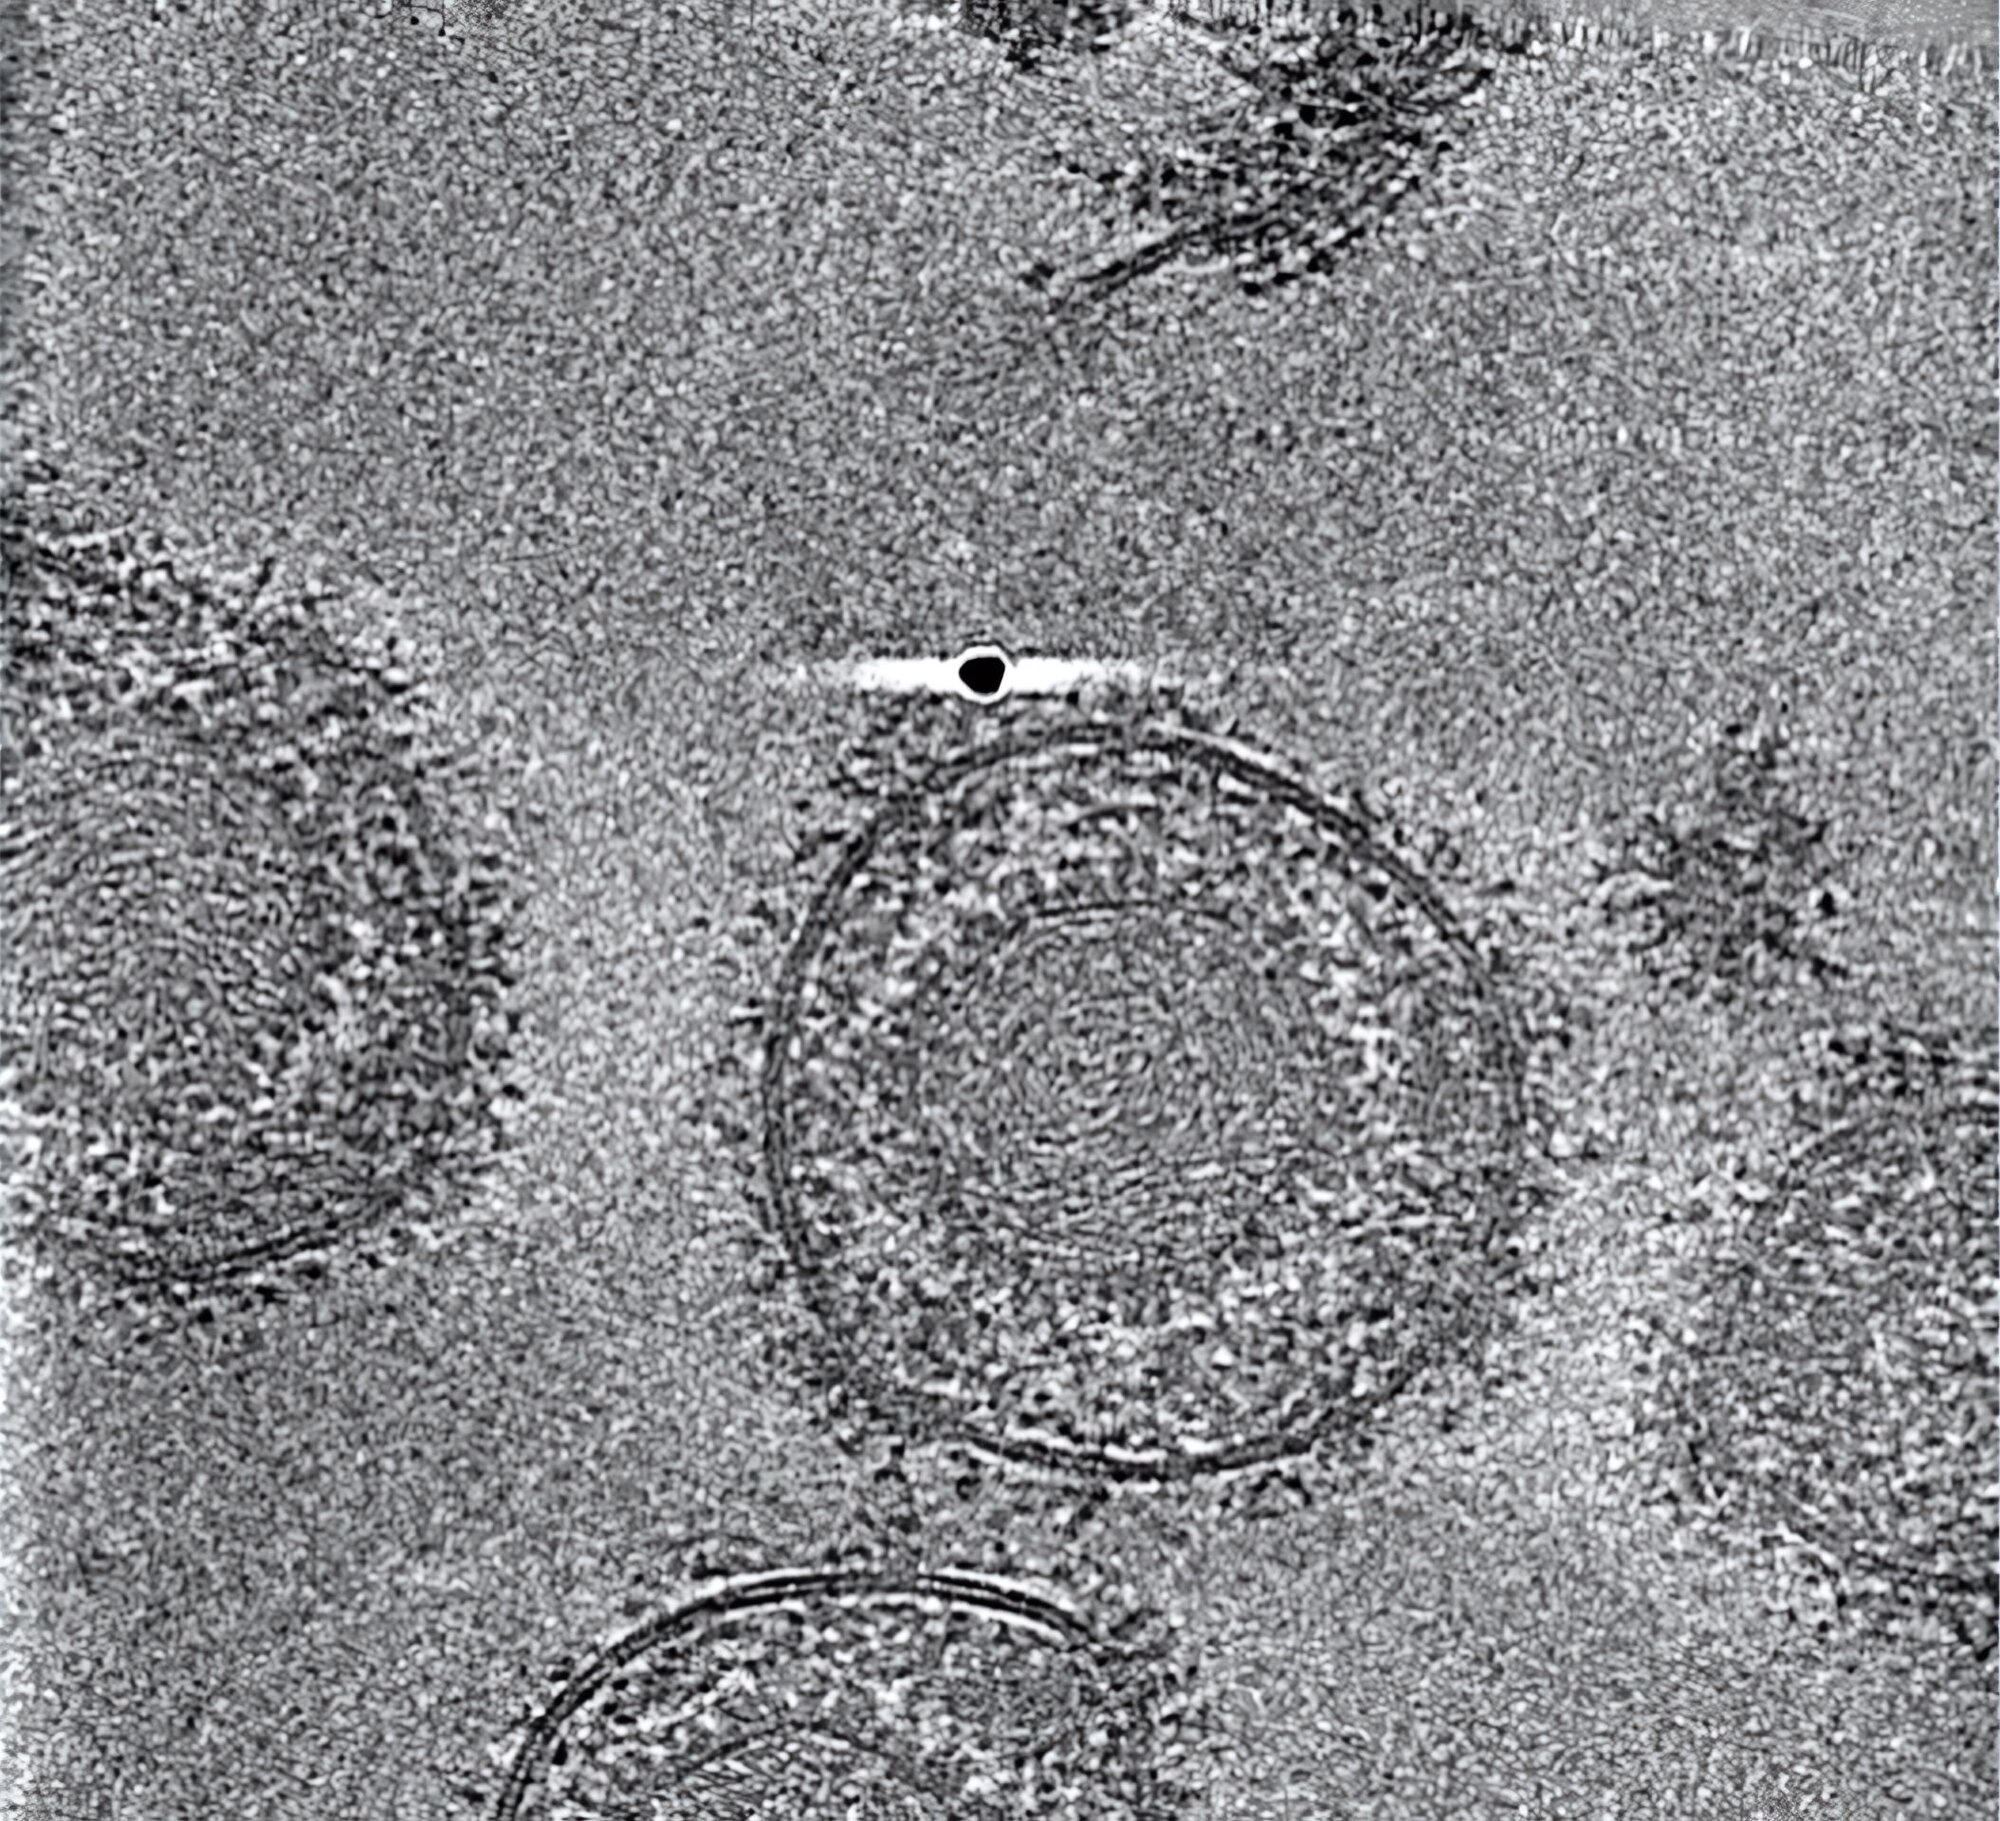

Forschende des Leibniz-Instituts für Virologie (LIV), der Universität Hamburg (UHH), und des Universitätsklinikums Hamburg-Eppendorf (UKE) am Centre for Structural Systems Biology (CSSB) in Hamburg sowie des Göttinger Max-Planck-Instituts (MPI) für Multidisziplinäre Naturwissenschaften ist es jedoch gelungen, den gB-Komplex in seiner bisher nicht zugänglichen fusionsbereiten Form zu stabilisieren. Sie konnten dessen hochaufgelöste Struktur mittels Kryo-Elektronenmikroskopie, Bildanalyse und Struktur-Modellierung bestimmen. Dabei haben die Technologieplattformen für ausgebaute Lichtmikroskopie und Kryo-Elektronenmikroskopie (Kryo-EM) am CSSB geholfen.